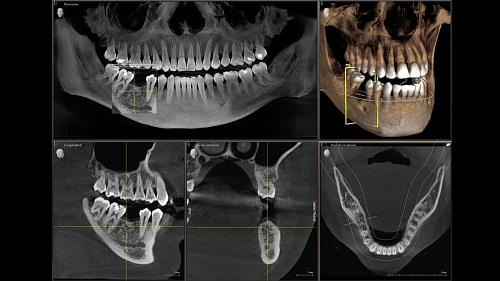

Диагностика последнего поколения, идеально решающая задачи рентгеновского обследования независимо от размеров клиники. Поля изображения зависят от определенной клинической картины, поэтому специалистам так удобно работать с ORTHOPHOS SL 3D. Данная установка делает объёмные картинки для одиночной реставрации в 3D качестве полностью всей челюсти такого размера, которого требуется.

ОБЪЁМ ДЛЯ ЛЮБЫХ ЦЕЛЕЙ

Планирование одиночной реставрации, эндодонтические исследования и пр. – для этого специалист может выбрать объёмные варианты 8 х 8 см или 11 х 10 см, также предлагается объём 5 х 5,5 см. Снимки в HD-качестве, стандартные настройки или выбор объёма обследования в зависимости от диагноза — всё это врач получает в отличном качестве, а для пациента излучение в районе исследования минимально.

Датчик прямого преобразования DCS

Конструктивные особенности датчика DCS заключаются в превращении рентгеновского излучения в электрическую энергию. Обычная для таких случаев промежуточная стадия светового луча отсутствует. Другими словами, значительно снизив потери сигнала, производитель максимально улучшил чёткость.

С технологией SL можно за один сеанс получить огромное количество снимков. Те из них, где фокусировка наиболее чёткая, автоматически соединяются. В итоге одна процедура — снимки челюсти полностью в самом лучшем качестве. Даже нестандартные случаи не станут помехой в обследовании. К примеру, при ретинированных зубах уже после того, как снимок сделан, нужную область можно выделить подробнее, и в ещё одном рентгене необходимость отпадает.